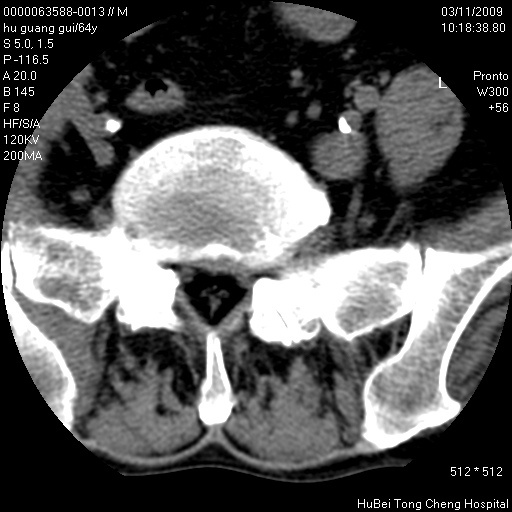

患者 男,64岁。腰痛十余天。(临床未提供其他病史)

临床诊断:腰痛原因待查(腰椎间盘突出症?)。

腰椎间盘ct轴位平扫(层厚5mm,层距4mm),图像如下:

腰椎退行性变,腰4—5椎间盘膨出。

右侧骶骨侧块骨侵蚀,骶髂关节骨性关节面破坏,并见软组织肿块,考虑骨转移瘤可能,进一步检查。

1.腰椎退行性变,腰4—5椎间盘膨出。

2.右侧骶骨侧块骨侵蚀,骶髂关节骨性关节面破坏,并见软组织肿块,考虑:脊索瘤,骨转移瘤可能,进一步检查。

1)腰椎退行性变,l4—5椎间盘膨出。2)骶骨右侧块骨转移瘤可能,3)水平骶椎。建议作一步检查。